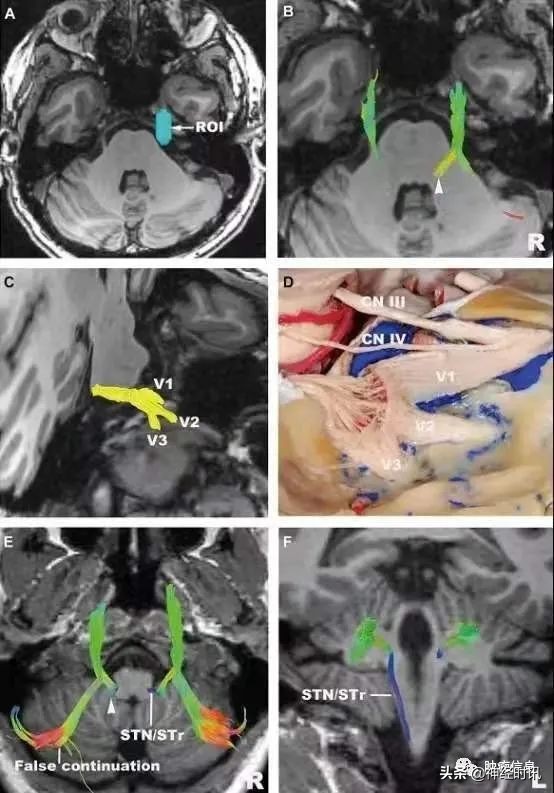

上图 :三叉神经。

A,感兴趣区选在桥前池部分;

B,高分辨率示踪三叉神经桥脑前段;

C,斜位观察高分辨率三叉神经,可重建出眼神经,上颌神经,下颌神经;

D,对应的解剖示意图;

E,F,水平位和冠状位三叉神经的高分辨率重建,左侧三叉神经到桥脑后结束,右侧三叉神经纤维进入小脑,这与正常解剖结构不符。

STN,脊髓三叉神经核;

STr,脊髓三叉神经束